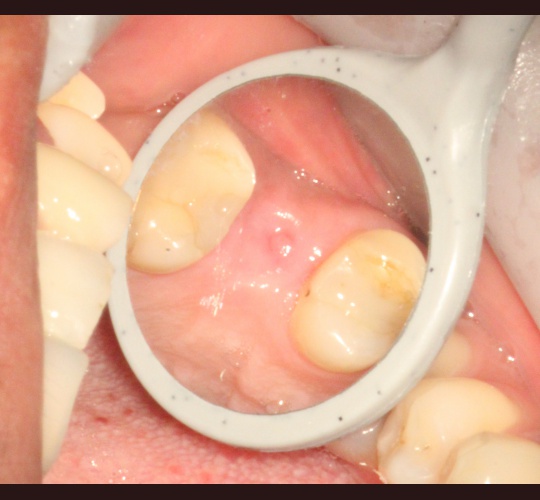

Implants: Case #4

Previous root canal from 2002 now diagnosed with a root fracture. Extraction was done and no bone graft was placed. After 4 months of healing incomplete healing has occurred. Defect was cleaned out and a Straumann implant was placed. The space adjacent to the implant was grafted with MFDBA and allowed to heal for 4 months then a healing cap was placed.